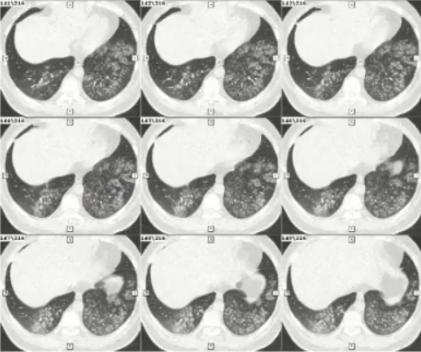

病例3

男,37岁,既往身体健康。因发热、咳嗽、咳黄痰1周入院。

日最高体温38.8℃-39.5℃,伴咽痛、肌痛、全身乏力,急诊血常规

WBC:8.74×109/L,N:0.865,予退热胶囊、头孢曲松、阿奇霉素等药物治疗3天无效。

CRP 12.10 mg/dl、PCT 0.107 ng/ml。

血清肺炎支原体抗体、肺炎衣原体抗体、军团菌抗体、流感病毒IgM均阴性。RT-PCR肺炎支原体核酸阳性。使用莫西沙星治疗14天后出院。

图3 双肺弥漫性小结节为主,中下肺布满粟粒样小结节,部分融合成片状

病原学诊断和转归

1. 病原学诊断

(1)入院次日BALF肺炎支原体核酸阳性

(2)血清肺炎支原体抗体,入院前为小于1:40;入院第14天为1:1280。

2. 转归

莫西沙星单药治疗2周后肺部阴影明显吸收

3. 诊断治疗面临的困难

• 临床表现不典型:咳黄痰

• 特殊的影像表现:中下肺弥漫小结节影

• 早期病原学检测无阳性发现

• 常规经验性治疗无效